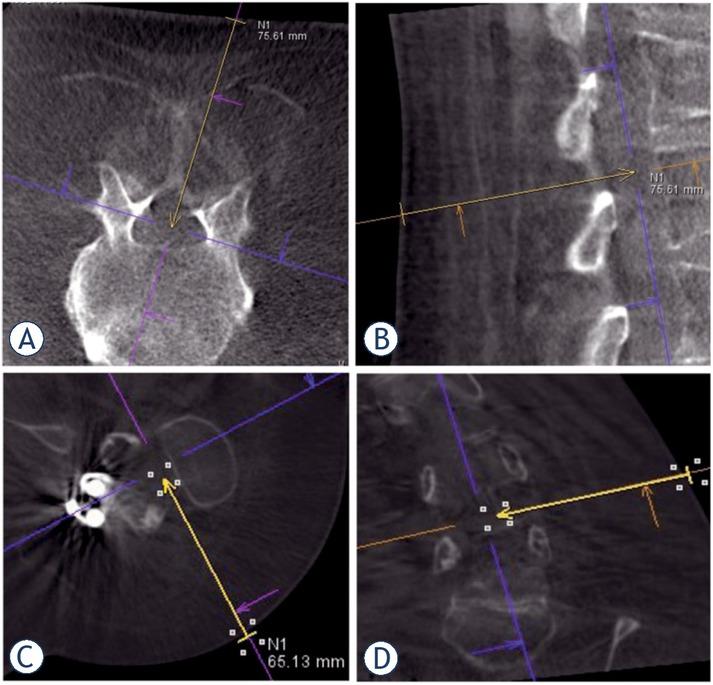

Integrated laser of the C-arm marked the entry position of the needle on the skin. The target point position was visualized under intermittent fluoroscopic guidance using two orthogonal views (Figures 1, 2, 3). Once the needle tip reached the target point, an aspiration of cerebrospinal fluid (CSF) was performed to confirm the intrathecal position. Afterwards, 5 ml of CSF was aspirated, and 5 ml nusinersen solution was intrathecally delivered according to the manufacturer’s instructions. After the procedure the patients were surveilled for 4-6 hours before being discharged.

Cone-beam CT orthogonal reconstructions demonstrating the planned needle trajectory. (A), (B). Planning the interlaminar approach (yellow arrows); (C), (D). Planning the transforaminal approach (yellow arrows).